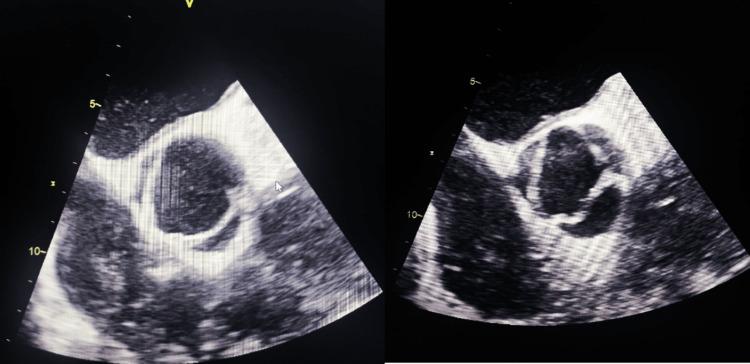

Coronary artery ectasia (CAE) is a rare condition, affecting 3%-8% of patients with atherosclerotic coronary artery disease, and is characterized by the abnormal dilatation of the coronary arteries. While the etiology of coronary artery ectasia encompasses a myriad of acquired and genetic factors, its pathogenesis still remains a subject of investigation. The clinical manifestations are varied, ranging from asymptomatic cases to chest angina and myocardial infarction. Coronary angiography remains the gold standard for diagnosing CAE. We herein report four cases of coronary ectasia: the first involving myocardial infarction, the second associated with bicuspid aortic valve with severe aortic regurgitation, the third detected during coronary angiography for moderate left ventricular dysfunction, and the last one detected during coronary angiography for stable angina. The aims of our study are to highlight the diversity of clinical presentations as well as the challenge of management, given that there are no universal treatments or guidelines.

冠状动脉扩张(CAE)是一种罕见病症,在动脉粥样硬化性冠状动脉疾病患者中占3%-8%,其特征为冠状动脉异常扩张。虽然冠状动脉扩张的病因包括众多后天因素和遗传因素,但其发病机制仍是一个研究课题。临床表现多样,从无症状病例到心绞痛和心肌梗死不等。冠状动脉造影仍然是诊断CAE的金标准。我们在此报告4例冠状动脉扩张病例:第一例伴有心肌梗死,第二例与二叶式主动脉瓣伴严重主动脉瓣反流相关,第三例在冠状动脉造影时因中度左心室功能障碍被检测出,最后一例在冠状动脉造影时因稳定型心绞痛被检测出。鉴于目前尚无通用的治疗方法或指南,我们研究的目的是强调临床表现的多样性以及管理方面的挑战。